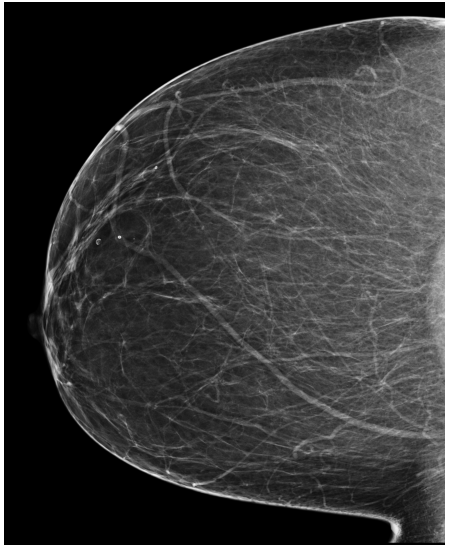

Refer to caption

(a) FeatAlign

(b) FeatAlignReg

(c) ImgFeatAlign/ImgAlign

(d) FeatAlign

(e) FeatAlignReg